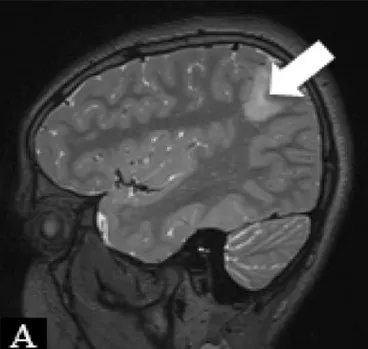

| Patient 1 | Pathology: Residual left-hemispheric pathology. |

|

| M, 12 years | Seizures: Daily asymmetric tonic spasms provoked by unexpected tactile and auditory stimuli. | ||

| Neurological examination: Mild right-sided hemiparesis. | |||

| MRI: Axial T2 with a small cortical remnant on the left parasagittal (white arrow in Figure A). | |||

| Wada test: Confirmed right leg motor functionality of the parasaggital cortical remnant. | |||

| Surgery: Modified hemispherotomy after intra-operative monitoring (IONM) and preservation of the right leg motor function (early sagittal CT showing the descending fibers from that area, white arrow on Figure B). | |||

| Follow-up: Early postoperative seizures for 1 week, then >1 year seizure-free. | |||